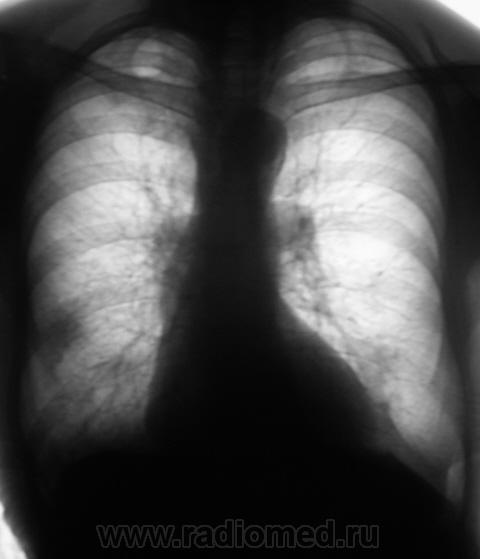

Динамика отрицательная.

Дмитрий